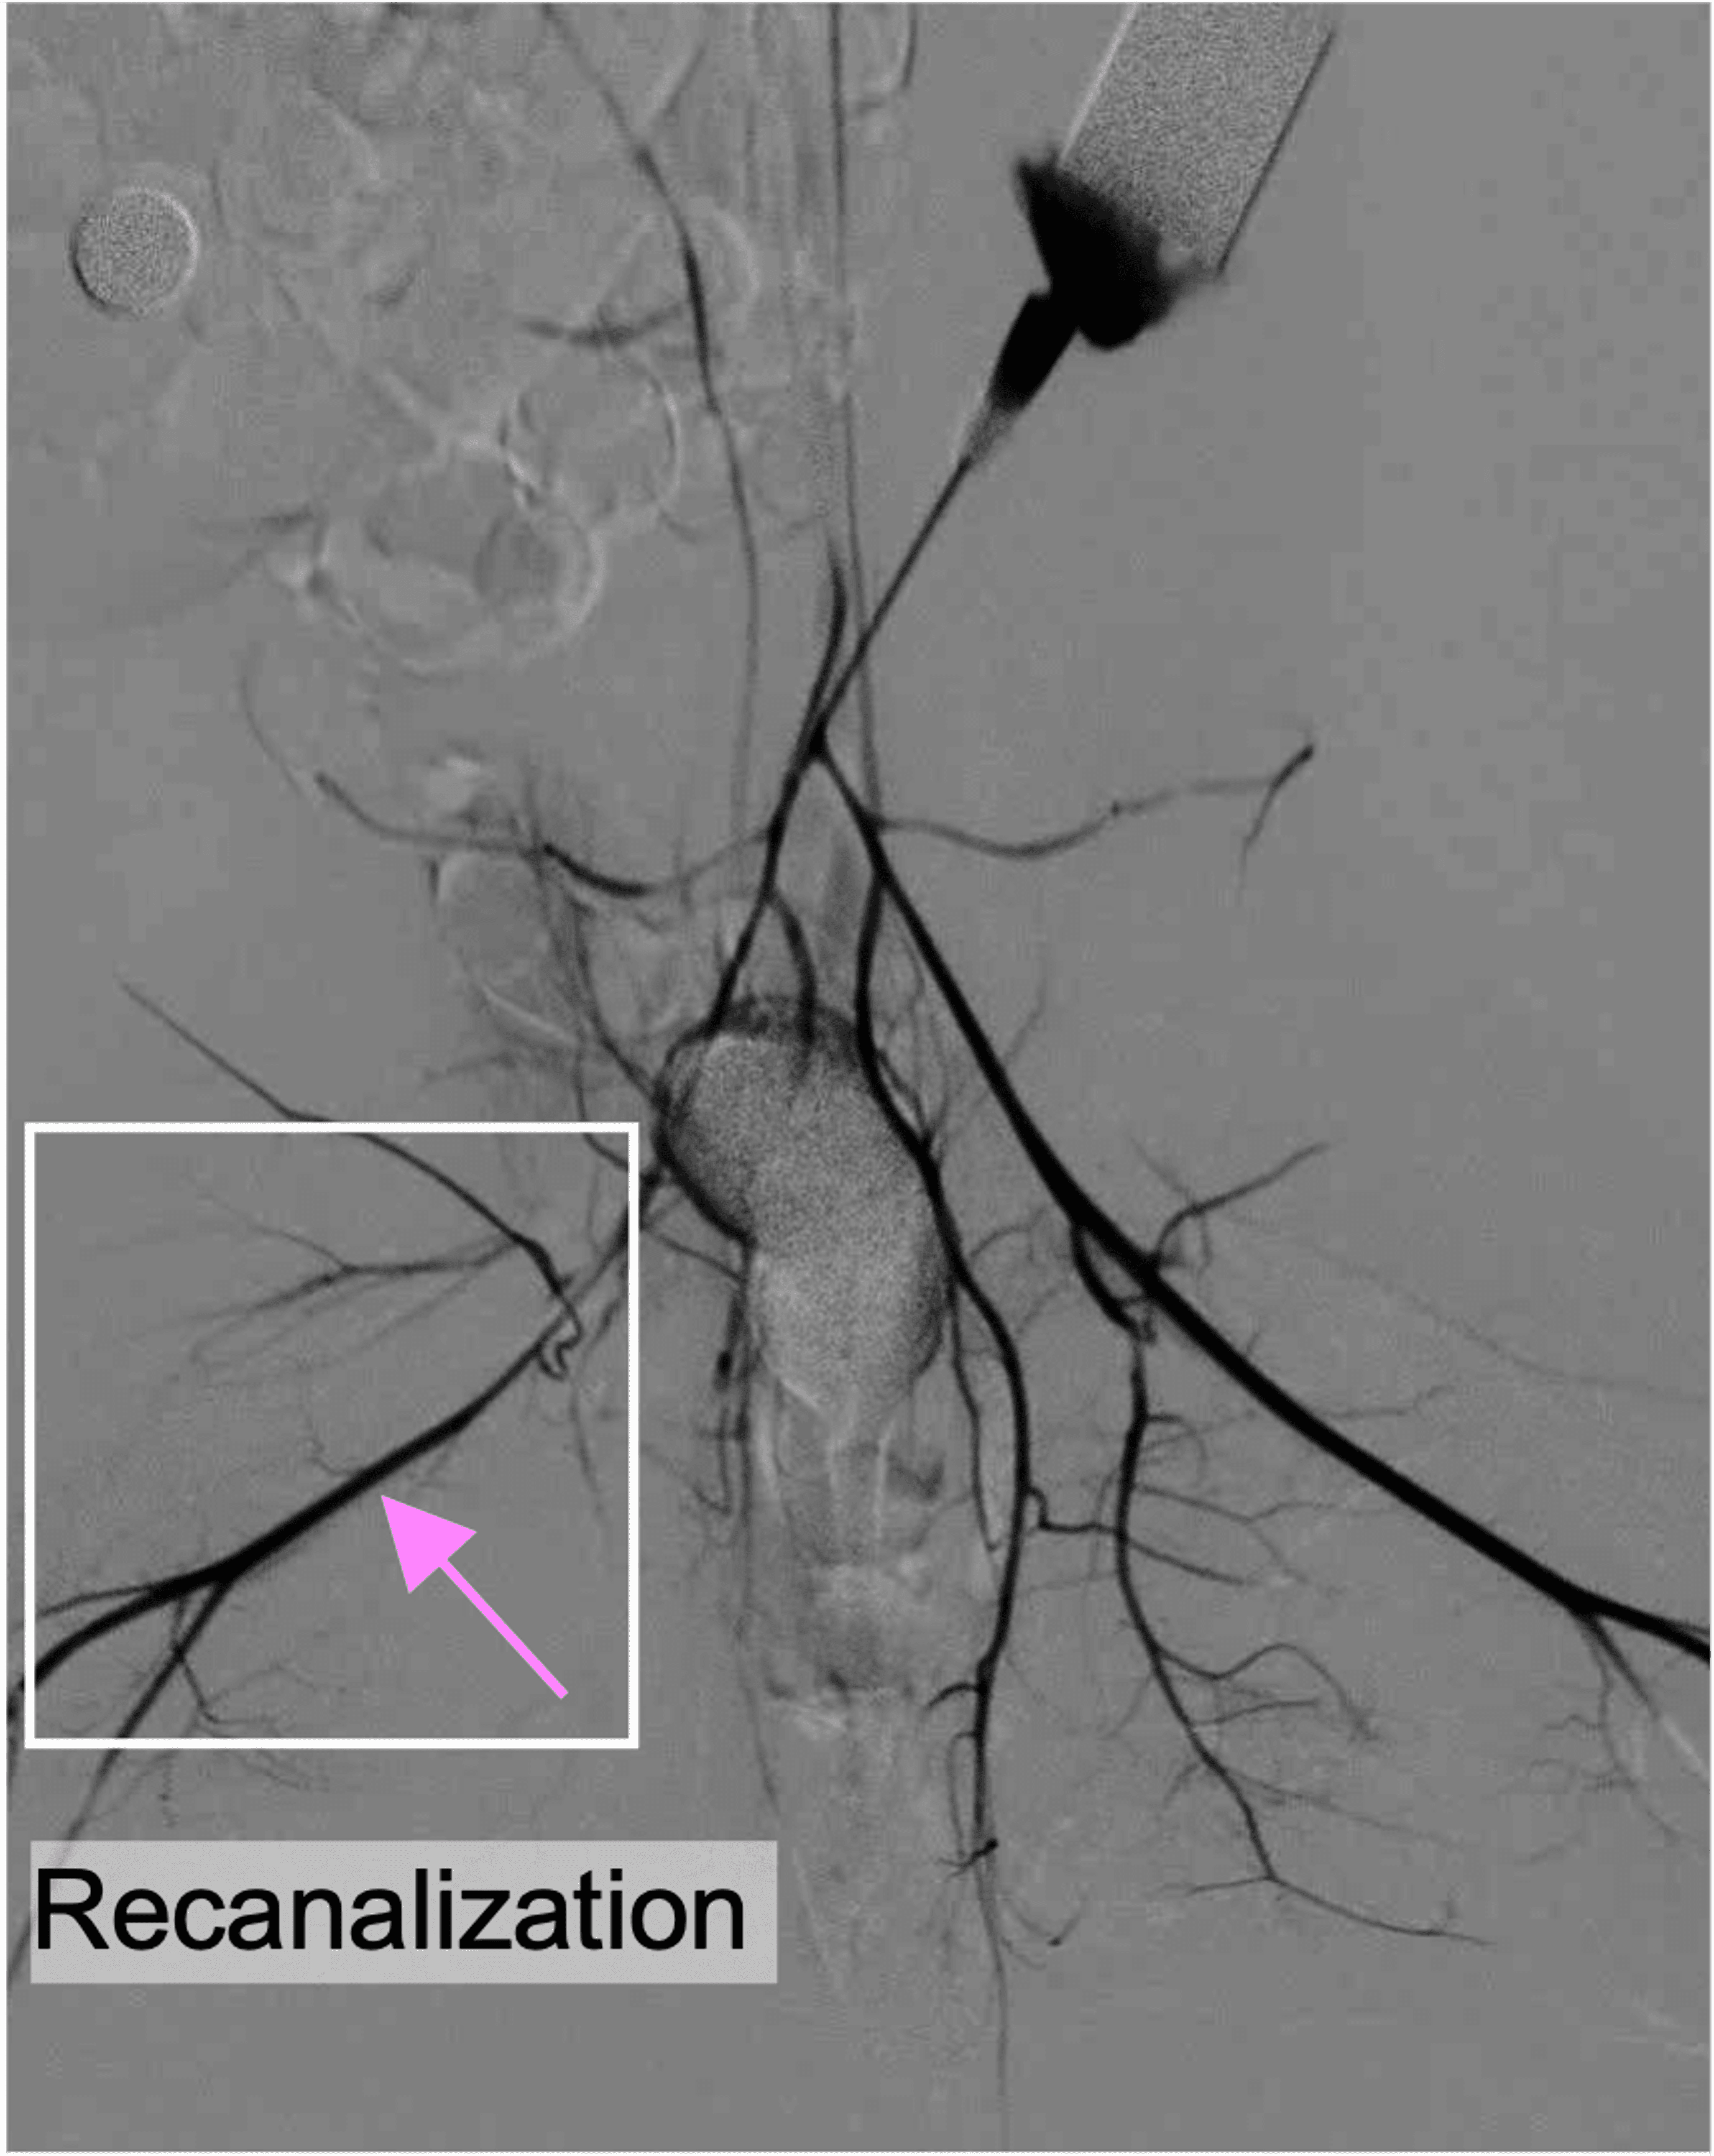

Our Solution

CardioCare

A first-in-class re-clinically validated catheter solution for PCI

SonoRobotics develops catheter-based ultrasound technology for thrombus disruption and microvascular protection in PCI workflows.